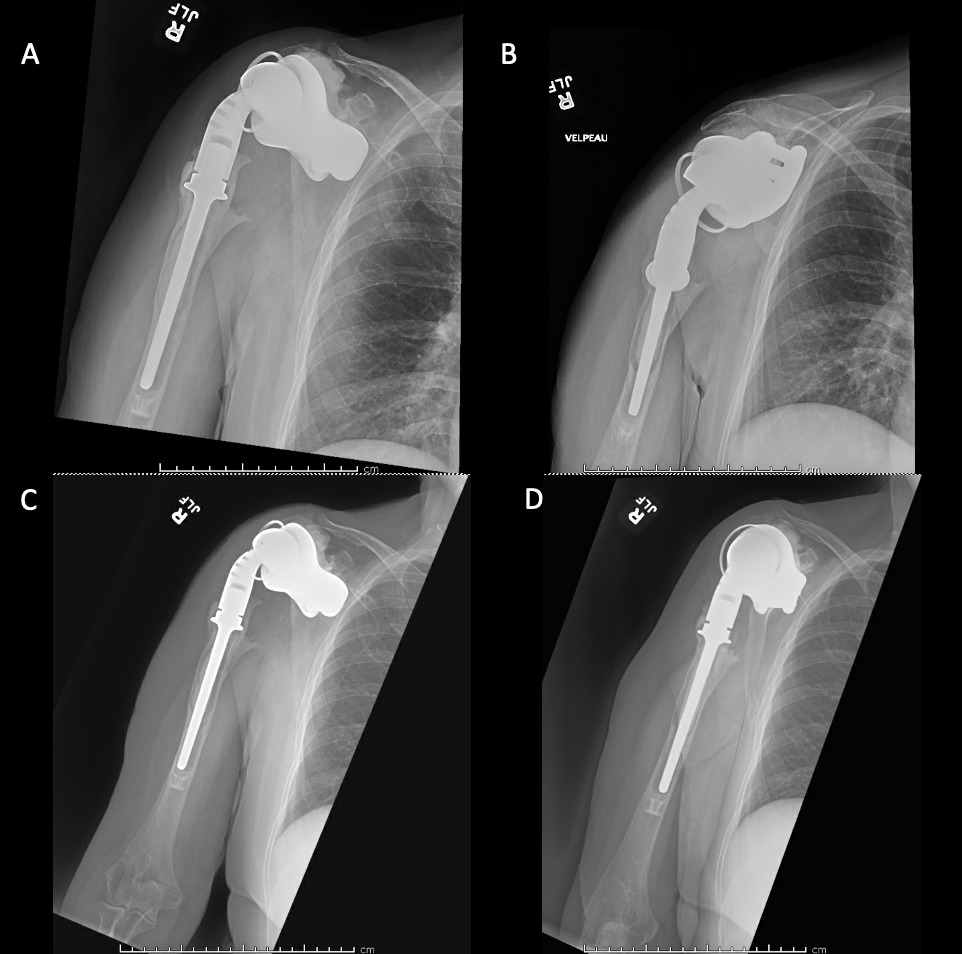

A 62-year-old woman presented for evaluation of her reconstructive options after resection arthroplasty of a right rTSA and completion of antibiotic treatment for culture negative PJI. Her rTSA had been an Encore prosthesis placed due to rotator cuff arthropathy (Figures 6). Post-operatively she had persistent pain, stiffness, and tenderness to palpation that was treated with physical therapy, a steroid injection, and manipulation under anesthesia. An infectious work up due to the chronic and persistent nature of the pain showed WBC 7.4, ESR 53, CRP 1.2. Patient denied further work up with a tagged white cell scan and preferred continued clinical monitoring to observe pattern of symptoms. Eleven months later, she endorsed persistent pain. Repeat infectious work up showed WBC 4.5, ESR 13, and CRP 1.1. Despite the normal inflammatory markers, a 10-day trial of Augmentin was initiated and failed to change her symptoms. The decision to proceed with 1 vs 2 stage reconstruction was made. During resection arthroplasty, a substantial amount of fluid was expressed from the joint capsule concerning for PJI. A cement spacer was placed, and the patient was treated with 6 weeks of vancomycin and cefepime (Figure 7). There was proximal humeral bone loss as the result of resection arthroplasty due to the humeral stem. The glenoid component was loose and associated with glenoid bone loss, further complicated by the need for removal of a broken central screw (Figure 8).

Intra-operative frozen sections, tissue cultures, and gram stain showed no signs of infection. Following treatment, inflammatory markers remained normal (WBC 5.5, ESR 22, CRP 0.9), and aspiration of the shoulder showed no organisms on gram stain and no growth on aerobic, anaerobic, fungal, and acid-fast bacilli cultures. Cultures were held for 21 days to rule out C. Acnes infection. She was left with profoundly limited active motion and severe pain and the patient elected to proceed with revision surgery. Because of the combination of severe glenoid and humeral bone loss and the lack of rotator cuff attachments necessitating a design with additional constraint, the decision to proceed with custom prosthesis design was made 9 weeks after resection arthroplasty.

Case 2. At the latest follow-up one-year post-op, the patient expressed that the pre-operative pain had resolved after the operation. Despite this, she stated that if given the option again she would not undergo the surgery because she did not attain the function she expected and felt that her function may have decreased compared to pre-op. Overall stability and alignment were good. On physical exam, she was able to reach within 1 inch from her mouth and had 20 degrees abduction and 5 degrees forward flexion actively. Active elbow flexion was 0 to 120 degrees (Figures 14). At 2 years post-op she had some regression in her pain but accompanied by modestly decreased AROM. Shoulder AROM was 15 degrees abduction, and 5 degrees forward flexion. Elbow AROM was from 0 to 105 degrees of elbow flexion. CT scan showed increased lucency surrounding the humeral component concerning for osteolysis and prosthesis loosening (Figure 14). Blood work at the 2-year mark to investigate the radiolucencies and decreased AROM left us with low suspicion for infection (WBC 5.4, ESR 33, CRP <3.0).